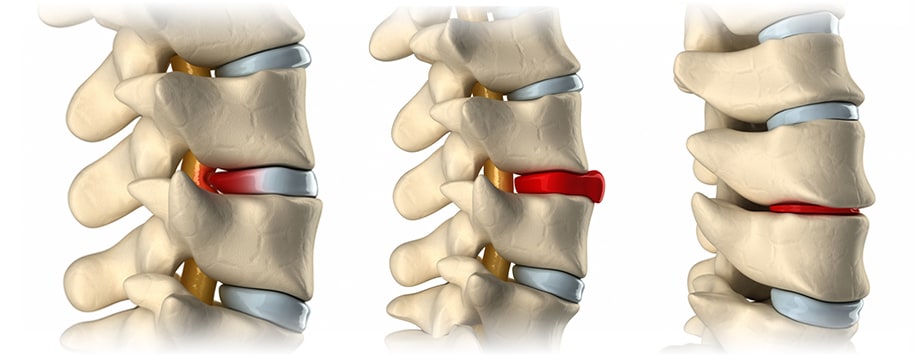

허리디스크는 척추 뼈 사이에서 충격을 흡수하는 디스크가 제자리에서 밀려나와 신경을 압박하면서 통증을 유발하는 질환을 의미합니다. 초기에는 단순 근육통처럼 뻐근하고 묵직한 느낌 정도로 시작되지만, 점차 엉덩이와 다리까지 저리고 당기는 방사통이 나타날 수 있습니다.

무거운 역도 운동, 특히 많은 하중이 가해지거나 척추에 무리를 주며, 허리가 비틀어지는 운동 등은 허리 디스크 환자에게 해로울 수 있습니다.

데드리프트, 무거운 웨이트를 동반하는 스쿼트, 오버헤드 프레스와 같은 운동은 디스크에 과도한 압력을 가하여 추간판 탈출증이나 디스크 관련 문제를 일으킬 수 있기 때문에 허리디스크가 있는 분들은 피하는 것이 좋습니다.